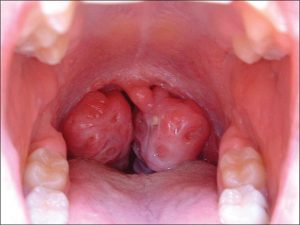

Amidan là một khối tân bào có cấu trúc như một cục thịt. Chúng là một bộ phận của vòng hạch bạch huyết nằm ở hai nên phía sau họng có tác dụng ngăn chặn vi khuẩn hay tác nhân khác xâm nhập vào cơ thể. Khi tác nhân tấn công ồ ạt sẽ khiến cho amidan quá phát dẫn đến sưng viêm. _________________________________________ |

Viêm amidan cấp tính:

Viêm amidan mãn tính:

- Biến chứng tại chỗ: Áp xe amidan, viêm tấy quanh amidan là những biến chứng tại chỗ thường gặp của bệnh viêm amidan. Hiện tượng này thường gặp ở các trường hợp bị viêm amidan cấp tính không sớm điều trị đã khiến bệnh tình chuyển sang giai đoạn nặng nề hơn;

- Triệu chứng: Đau họng, sốt, sưng amidan, khó nuốt